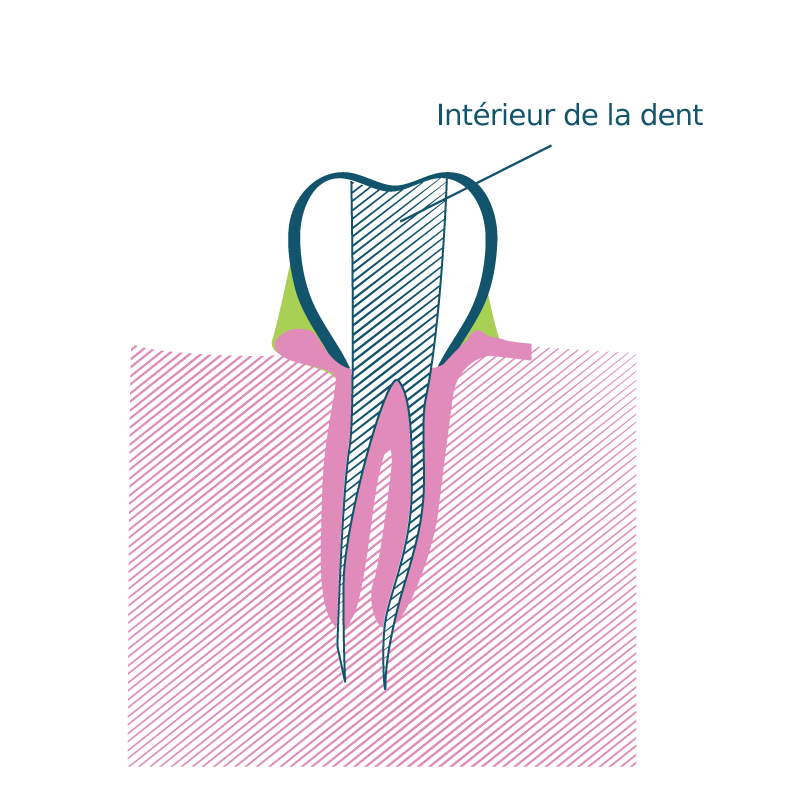

L’endodontie est la partie de l’odontologie qui traite de l’intérieur de la dent

Un traitement endodontique est réalisé lorsque des bactéries colonisent l’intérieur de la dent. Les canaux sont nettoyés selon un protocole précis. L’endodonte (intérieur de la dent) est ensuite obturé pour assurer la pérennité de cette désinfection (mécanique et chimique). Une fois les canaux remplis et étanches, un pansement provisoire est posé. La dent sera reconstituée de façon étanche et durable par le chirurgien-dentiste traitant. La dent sera reconstituée de façon étanche et durable par le chirurgien-dentiste traitant.